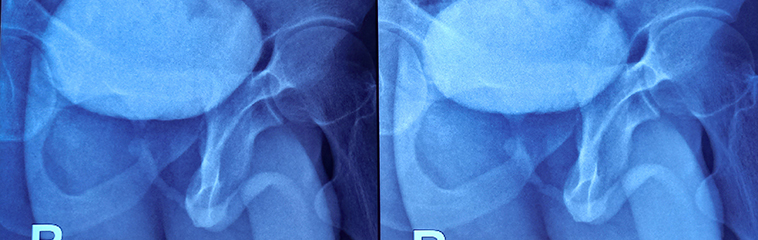

- Uretrografía retrógrada y miccional (más usada en varones): muestra la localización y longitud de la estenosis. Es la prueba de referencia para valorar la estenosis de uretra. Consiste en introducir contraste mediante una sonda colocada en el extremo más externo de la uretra, realizar radiografías mientras se introduce el contraste líquido, y realizar radiografías mientras el paciente orina.